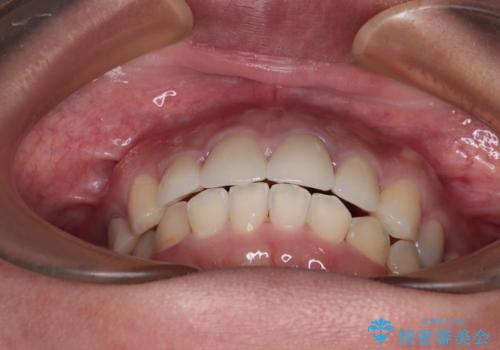

下顎の小臼歯を移動しきるのに2年弱の期間を要することとなり、補綴治療も合わせて2年半ほどの治療期間となりました。

口元の印象が大きく改善し、患者様には大変満足していただけました。